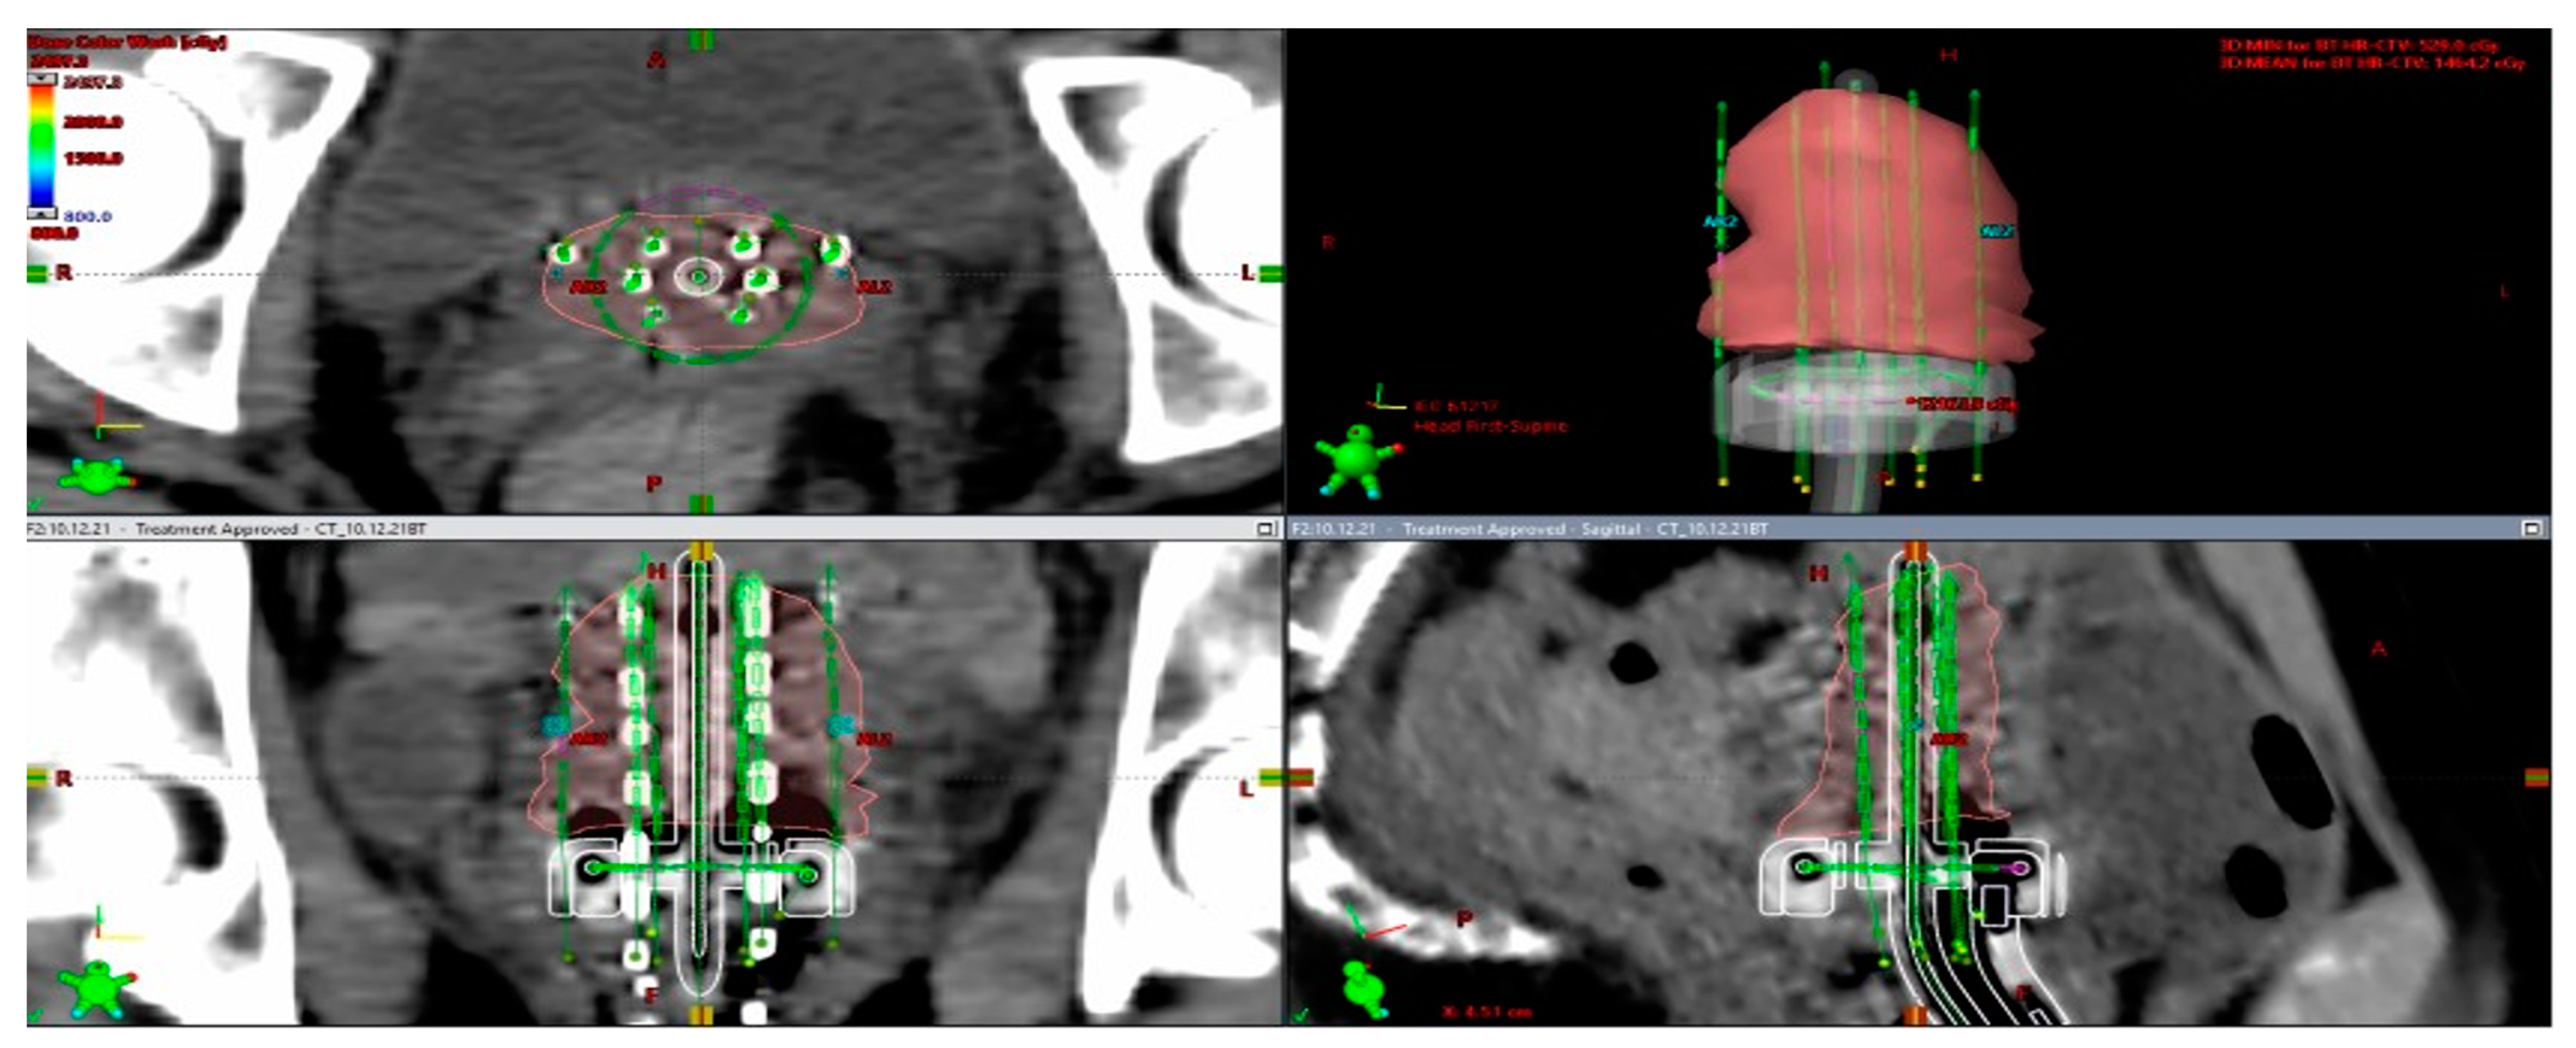

- Fortin, I.; Tanderup, K.; Haie-Meder, C.; Lindegaard, J.C.; Mahantshetty, U.; Segedin, B.; Jürgenliemk-Schulz, I.M.; Hoskin, P.; Kirisits, C.; Potter, R.; et al. Image-guided brachytherapy in cervical cancer: A comparison between intracavitary and combined intracavitary/interstitial brachytherapy in regard to doses to HR CTV, OARs and late morbidity—Early results from the Embrace study in 999 patients. Brachytherapy 2016, 15, S21. [Google Scholar] [CrossRef]

- Dimopoulos, J.C.; Kirisits, C.; Petric, P.; Georg, P.; Lang, S.; Berger, D.; Potter, R. The Vienna applicator for combined intracavitary and interstitial brachytherapy of cervical cancer: Clinical feasibility and preliminary results. Int. J. Radiat. Oncol. Biol. Phys. 2006, 66, 83–90. [Google Scholar] [CrossRef] [PubMed]